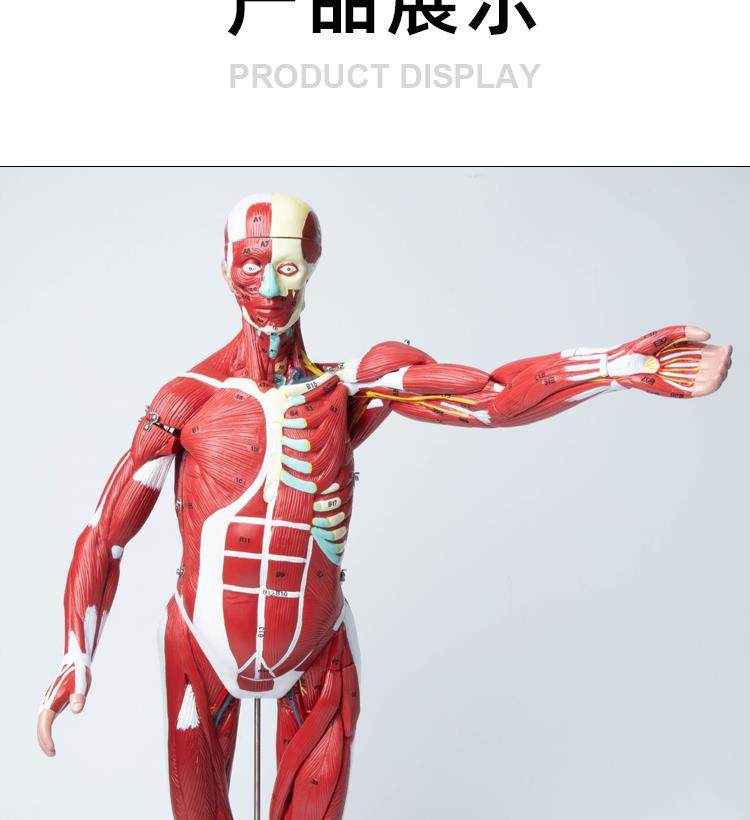

Human Body Muscle Internal Organ Disassembly Anatomy Structure Model Tissue Exercise Artificial Medical Teaching Aids

| Product Specifications | |

| Brand | No Brand (No Registered Trademark) |

| Model | 6622 |

| Color Classification | 85 Human Muscle Internal Organs Removable Organ,50cm Muscle Model |